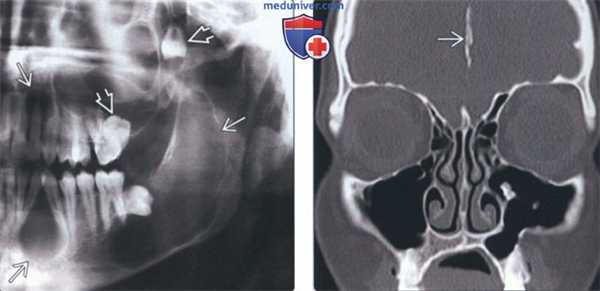

• Ранняя кальцификация серпа мозга, намета мозжечка, периклиноидных связок (дуральные «мостики»), твердой и мягкой мозговых оболочек, сосудистых сплетений, базальных ганглиев(а) МРТ, Т2-ВИ, корональный срез: классический СБКН. Визуализируется исходящая из альвеолярного отростка левой верхней челюсти большая однокамерная гиперинтенсивная на Т2-ВИ киста.

Киста выступает в верхнечелюстную пазуху, смещая дно пазухи и секрет кверху. Дифференцировать ретенционную кисту слизистой оболочки гайморовой пазухи от кисты альвеолярного отростка/зубной кисты наиболее удобно на корональных изображениях.

(б) MPT, Т1 -ВИ, корональный срез: визуализируется гипоинтенсивное на Т1-ВИ кистозное объемное образование. На данном изображении дно пазухи визуализируется хуже, чем при корональном Т2-ВИ. (а) Бесконтрастная КТ, аксиальный срез: у 16-летнего пациента с СБКН визуализируется протяженная кальцификация ламинарного характера серпа мозга и намета мозжечка. В правой височной доле визуализируется дефект вследствие резекции конвекситальной менингиомы.

(Слева) На кадрированной панорамной рентгенограмме визуализируются как минимум четыре кистозных образования челюстей слева. В задних отделах верхней челюсти смещенные моляры видны отчетливее, чем очаг. Множественные очаги в челюстях, напоминающие кисты, подозрительны на синдром базальноклеточного невуса (СБКН).

(Справа) На корональной КТ в костном окне у пациента с СБКН определяется обызвествление серповидной связки мозга. Эта находка считается нормальной, тем не менее, у пациентов с СБКН она обнаруживается намного раньше.2. Рентгенография при синдроме базальноклеточного невуса челюсти: